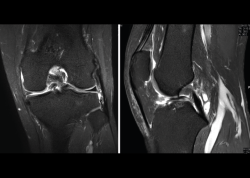

4.3. Osteocondritis

En la osteocondritis se aprecia una lesión subcondral caracterizada por resorción ósea, colapso y la formación de un secuestro.

El estudio por RM es una herramienta valiosa para diagnosticar e identificar las lesiones del cartílago. Conocer el aspecto del cartílago y saber cuánto y cuándo se lesiona, basándose en las clasificaciones actuales, permiten al radiólogo proporcionar la máxima información al clínico(20).

Figura 53. Corte de secuencia sagital (A) y axial (B) T2 Fat-Sat de RM de rodilla: lesiones osteocondrales en el fémur y la rótula.

Numerosos estudios demuestran la utilidad de la RM para definir la estabilidad o inestabilidad de la lesión en la osteocondritis, destacando su carácter no invasivo y la capacidad de valorar la progresión y la respuesta al tratamiento(21)(Figuras 53 y 54).

Figura 54. Corte de secuencia T1 y T2 Fat-Sat coronal de resonancia magnética: gran osteocondritis en el cóndilo femoral interno con edema en la medular adyacente.